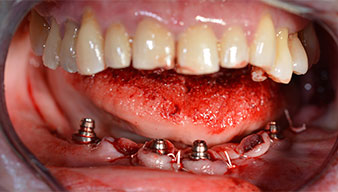

Abb. 14

Um die Divergenz der distalen Implantate auszugleichen, werden abgewinkelte Abutments (35 Grad) eingeschraubt, sodass die Austrittsprofile sämtlicher Implantate möglichst senkrecht zur Kauebene stehen. Dies ist Voraussetzung, um die provisorische und später auch die endgültige Versorgung okklusal verschrauben zu können (Abb. 15 und 16).

Implantate

Abb. 15

Abb. 16